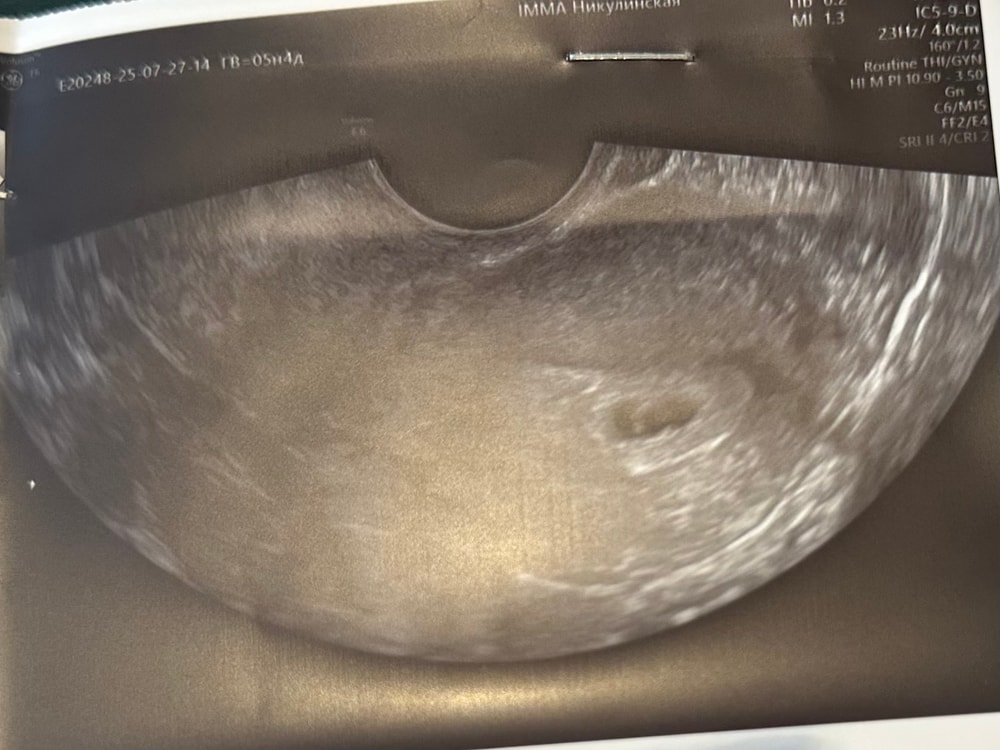

Результаты УЗИДевочки у меня паника , с ре договаривались об узи на 23 дпп , но я не выдержала решила пойти раньше в клинику рядом с домом. Узистка так меня испугала сказала есть тонус, ПЯ вытянутое , тип так не должно быть . Вроде ничего не болит выделений нет размеры пя 8.2 мм, жм 3.00 эмбрион пока не виден( очень боюсь теперь

Посмотрите на форму моего ПЯ.Никто не говорил ни за какой тонус,все хорошо Слава Богу!

Тут 5.6 недель